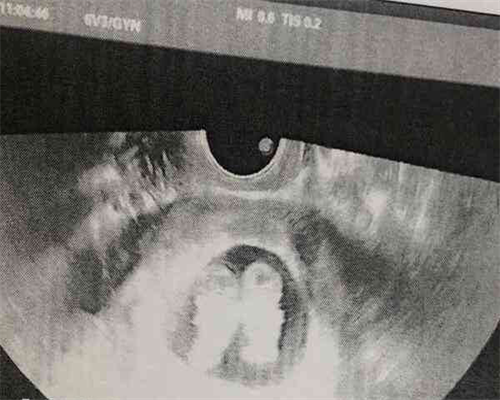

专家亲自操作,取精取卵!

专家亲自操作,胚胎移植!